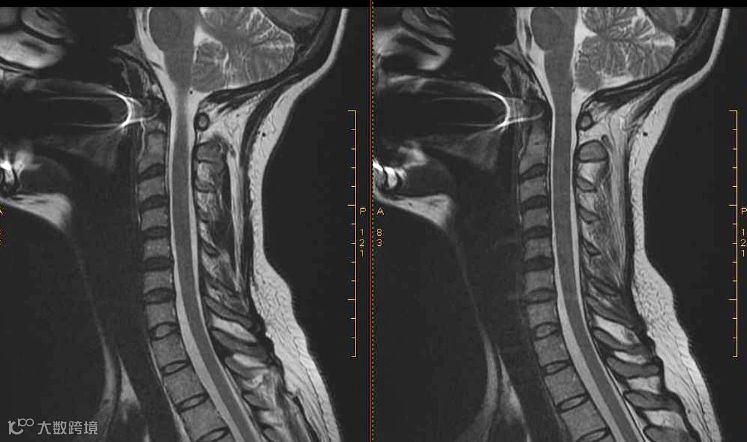

颈椎的核磁共振图像

核磁共振的另一特点是流动液体不产生信号,称为流动效应或流动空白效应。血液由于流动迅速,使发射MR信号的氢原子核离开接收范围之外,所以测不到MR信号,因此血管是灰白色管状结构,而血液为无信号的黑色。这样使血管很容易与软组织分开。

另外,磁共振成像还可获得人体横面、冠状面、矢状面及任何方向断面的图像,有利于病变的三维定位。